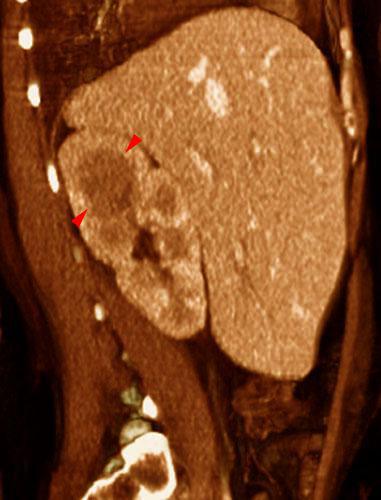

Abscesos renales en pionefrosis